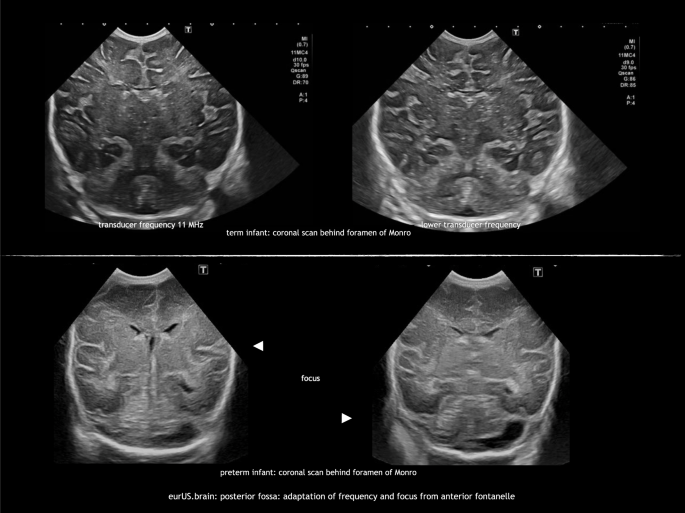

Adaptation of settings

The standard transducer frequency for neonatal CUS is 8–11 MHz. This frequency provides high-resolution images of the ventricular system, periventricular white matter, and deep gray matter structures. In extremely small, preterm infants, these settings also allow visualization of the posterior fossa, but in larger infants penetration is often insufficient. As a first step to improve image quality, one or more focus points can be aimed at the infratentorial region. In addition, decreasing the transducer frequency (5–6 MHz) will result in a better penetration of the ultrasound beam. However, lower frequencies reduce the resolution of the ultrasound image (Fig. 1).10